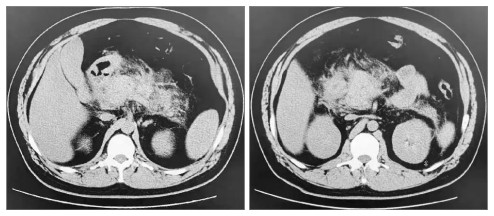

如图 2、图 3示:行血浆置换及CRRT治疗后,患者TG水平明显下降,腹痛也随之改善。患者于EICU共治疗4 d后一般情况显著改善,遂转入普通病区治疗。于入院第8日复查腹部CT可见胰周渗出较前吸收(见图 4),次日出院。出院后继续口服非诺贝特,3个月后随访查腹部CT可见患者胰腺体积、形态基本恢复,胰周渗出基本吸收,见图 5。

| 左图为胰尾;右图为胰头 图 5 出院3个月后上腹部CT |